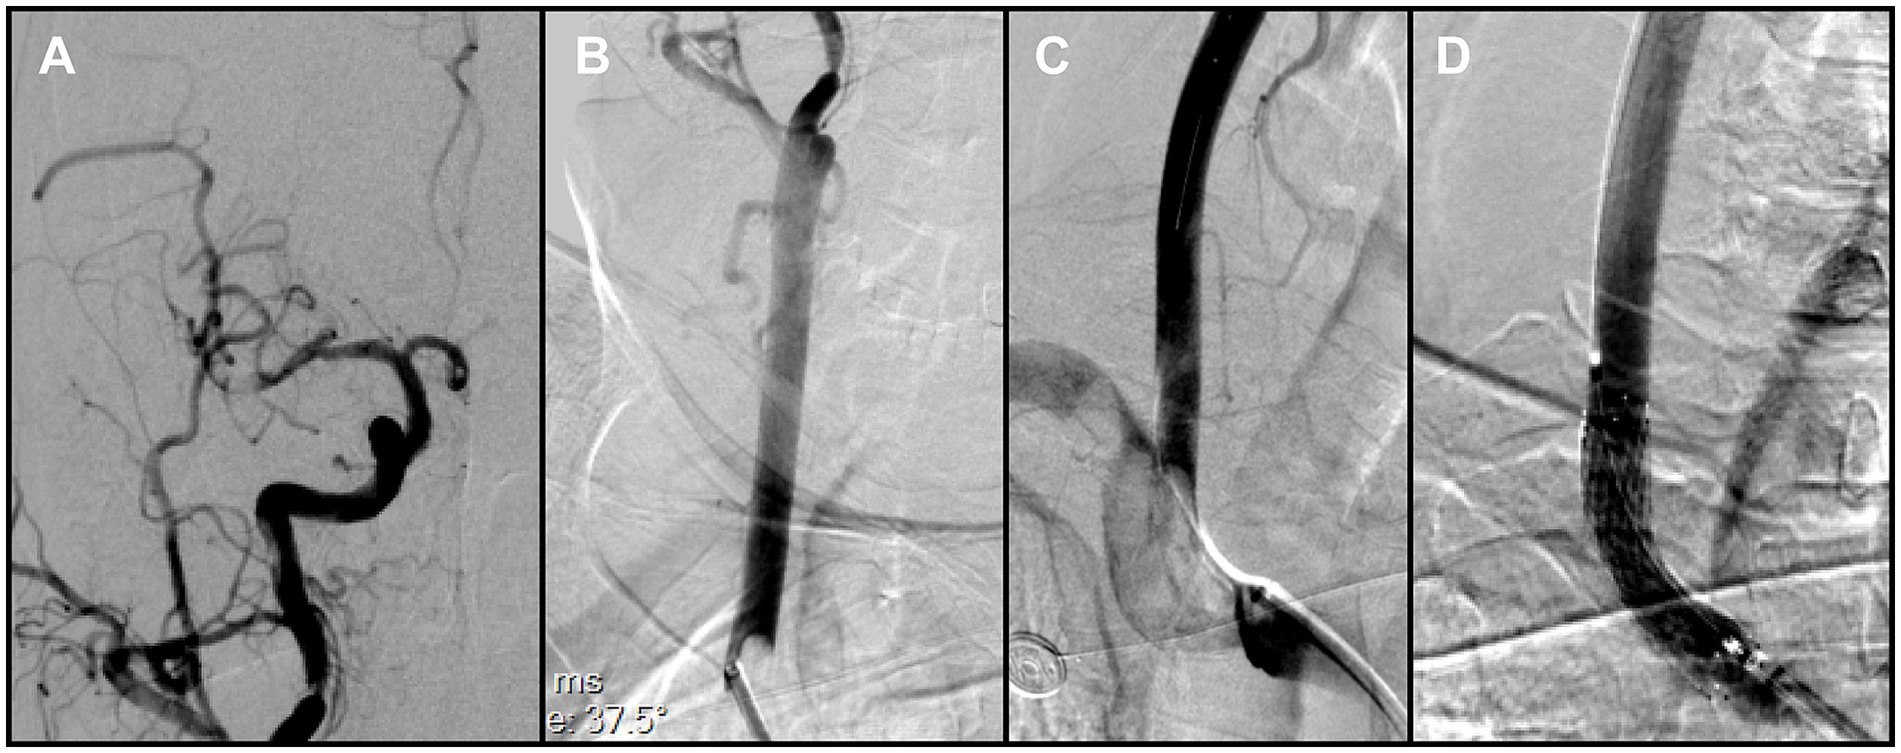

During this phase, impaired backflow in the Neuron MAX catheter was observed. After the catheter was withdrawn to the common carotid artery, adequate backflow through the guiding catheter was restored. Catheter angiography demonstrated severe vasospasm of the right ICA, explaining the earlier loss of backflow. In addition, a small residual thrombus was detected in the distal M1 segment (Figure 3A), and a previously unrecognized thrombus was identified in the right CCA (Figure 3B). After discussion, the team decided to prioritize treatment of the intracranial lesion. However, when the catheter was advanced into the ICA for follow-up angiography, the residual thrombus was found to have migrated spontaneously into an M4 cortical branch, and the ICA vasospasm had also resolved spontaneously. At that point, intracranial reperfusion was satisfactory, with an mTICI score of 2b, and no further treatment was required.

Figure 3. (A) Right common carotid angiography showed a small residual thrombus at the distal right middle cerebral artery (MCA) that did not significantly compromise hemodynamics. (B) A large thrombus was identified in the right common carotid artery, adjacent to the delivery catheter. (C) Brachiocephalic angiography with distal protection demonstrated a large free-floating thrombus (FFT) involving the brachiocephalic bifurcation, extending into the origins of the right common carotid and right subclavian arteries. (D) Post-stenting angiography demonstrated full expansion of the stent in the right common carotid artery (CCA), without residual stenosis at the treatment site.

2.4 Management of proximal FFT

To reduce the risk of embolization during assessment of the proximal vessels, a Solitaire stent retriever was temporarily deployed in the ICA to provide distal protection. As the Neuron MAX catheter was withdrawn to the brachiocephalic artery for angiography, a large FFT, corresponding to the lesion previously noted in the right CCA but only partially visualized, was clearly delineated at the brachiocephalic bifurcation, involving the origins of both the right subclavian artery and the right common carotid artery (Figure 3C). This thrombus at the brachiocephalic bifurcation was considered pre-existing, since no manipulation of the right subclavian artery had occurred before this angiogram.

Because en bloc retrieval across the bifurcation carried high risk of embolic escape and recurrent cerebral embolism, an in situ stabilization strategy was selected. Under distal protection with a SpiderFX device, a self-expanding PROTÉGÉ 9 × 40 mm stent (Medtronic, USA) was deployed in the CCA to pin and compress the thrombus against the vessel wall without predilation. Post-deployment angiography confirmed the ICA remained widely patent, with no residual stenosis (Figure 3D). The previously noted intracranial emboli had resolved spontaneously, and the final reperfusion grade improved to mTICI 2C (Figures 4A,B). Before completion of the procedure, angiography of the left vertebral artery demonstrated patent posterior circulation vessels with retrograde opacification of the right vertebral artery, indicating preserved collateral flow and minimal risk of thrombus migration from the right subclavian artery into the intracranial circulation (Figure 4C).